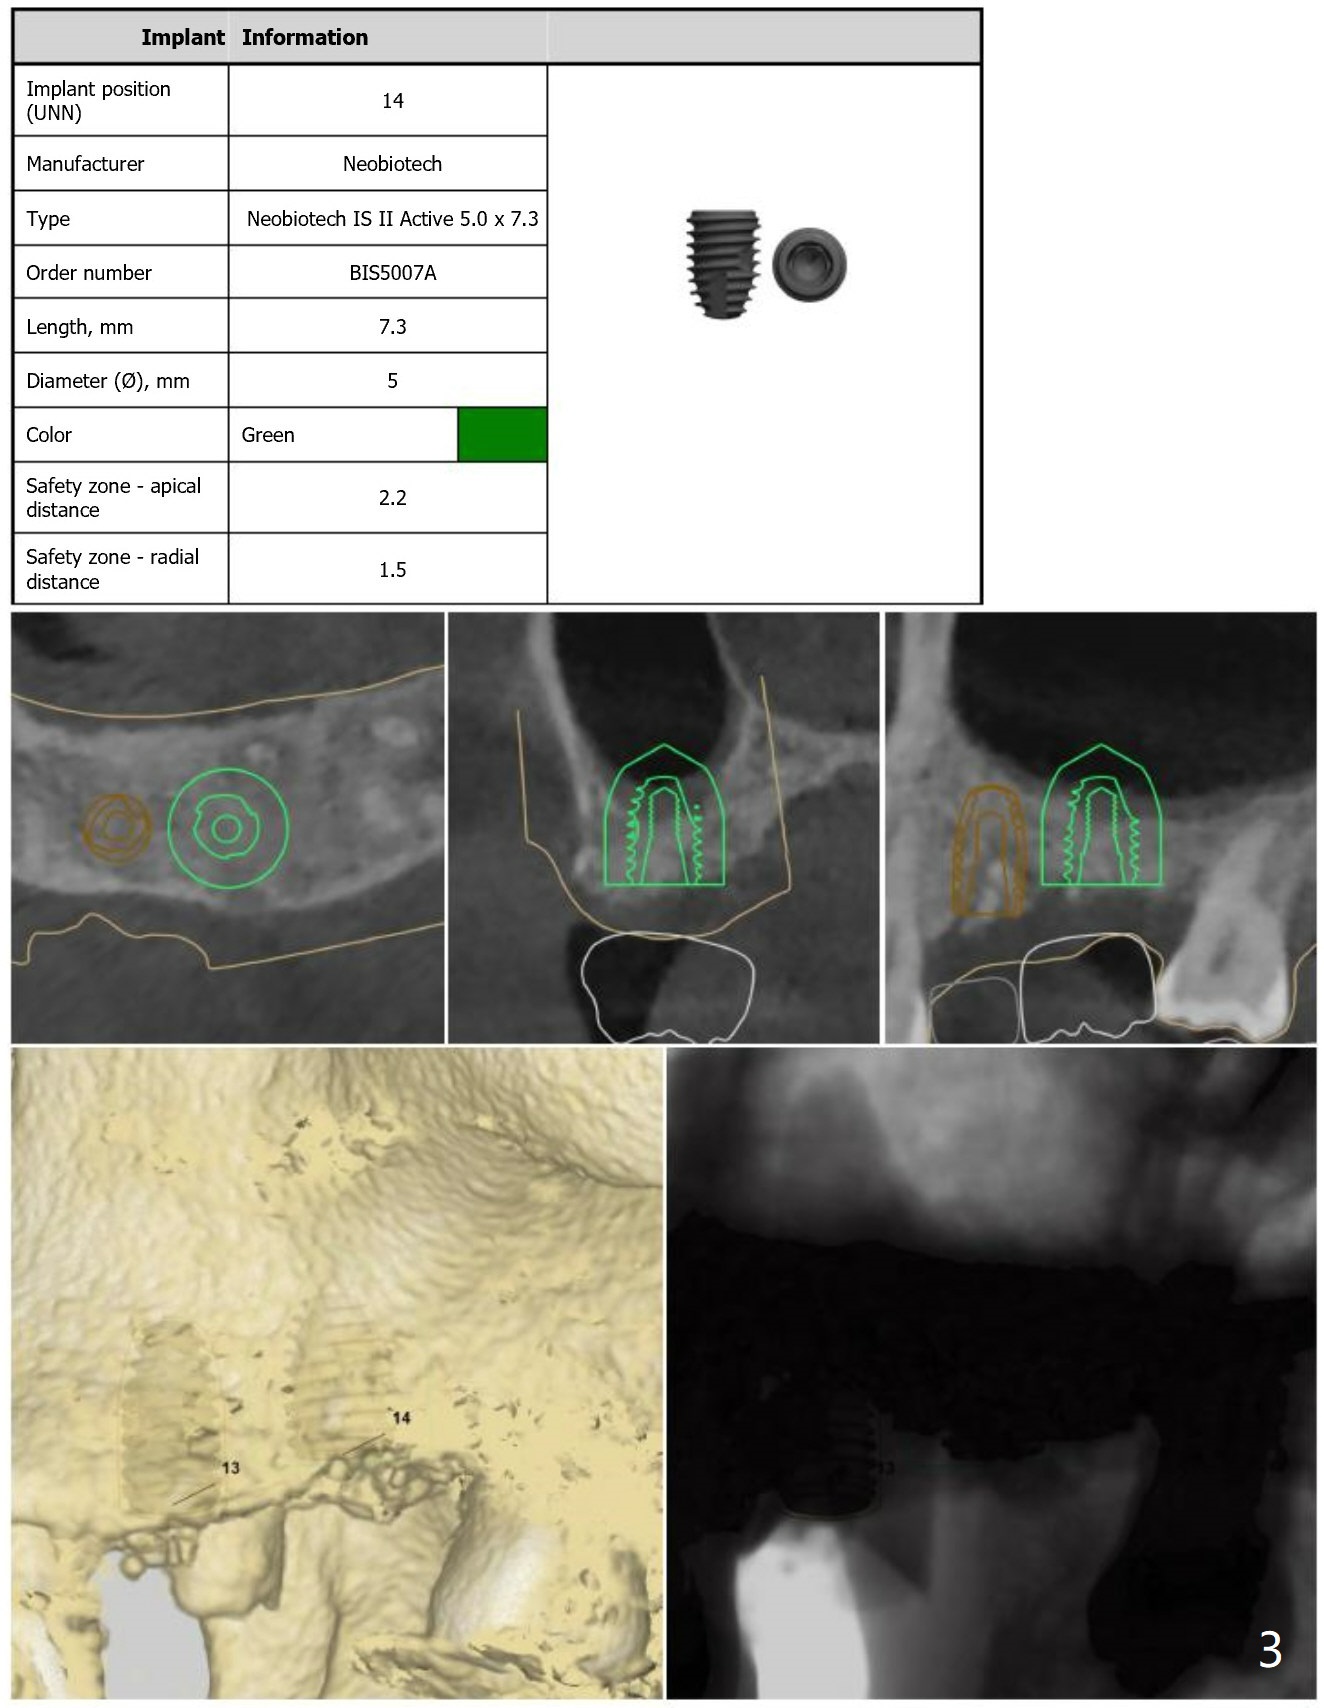

Short Implants with Sinus Lift at #14

Return to Upper Molar Immediate Implant, Armaments

Xin Wei, DDS, PhD, MS 1st edition 08/14/2018, last revision 08/30/2018